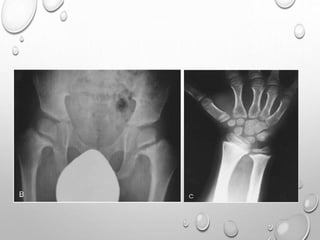

PELVIS

SMALL

ILIA ARE SHORT CAUDALLY

HORIZONTALLY PLACED ACETABULLA , THICKENED Y CARTILAGE

LIMBS

UL> LL

RHIZOMELIC TYPE

METAPHYSIS …..SPLAYING , CUPPING

GENU VERUM

TRIDENT HAND

TIBIA , ULNA ARE MORE SHORTENED THAN FIBULA , RADIUS

V SHAPED NOTCH IN GROWTH PLATE

SHORT , TUBULAR LONG BONES OF HAND AND FEET

FINGERS ARE OF SAME LENGTH

• 1. DYSPLASTIC OR SQUARE

ILIAC BONES

2. NARROW SACRO-SCIATIC

NOTCHES

3. FLAT BILATERAL

ACETABULAR ROOFS

4. SHORT BOTH FEMORAL

NECKS

5. CHAMPAGNE GLASS-

SHAPED PELVIC CAVITY